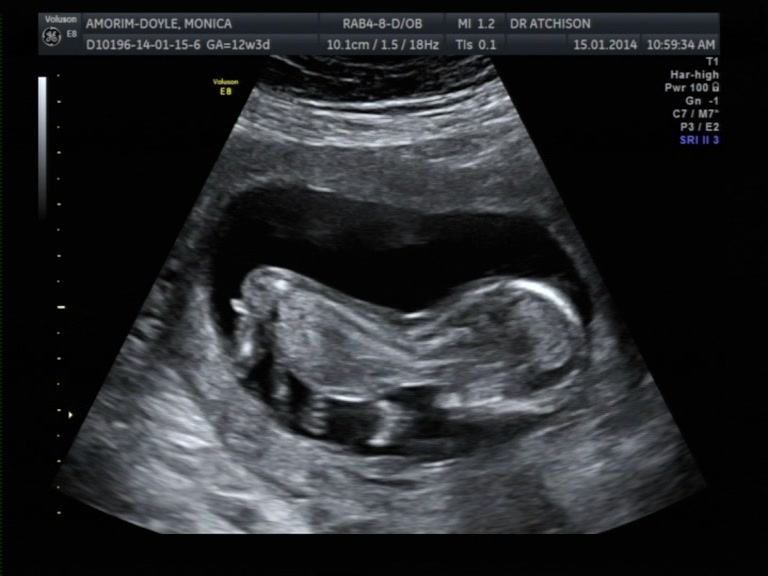

I already posted my ulstrasound picture but nub couldn't be seen, and as the obsessive human being I am I took pictures frame by frame using the video and I came up with some nub shots, BUT, I am not sure how to or even if I should regard a nub when baby is tummy down. I heard you 'read' the nub in relation to the spine. If you have a guess, regardless, I would be very happy. :)

Attachment 16360

IT'S A GIRL!!!!!!!